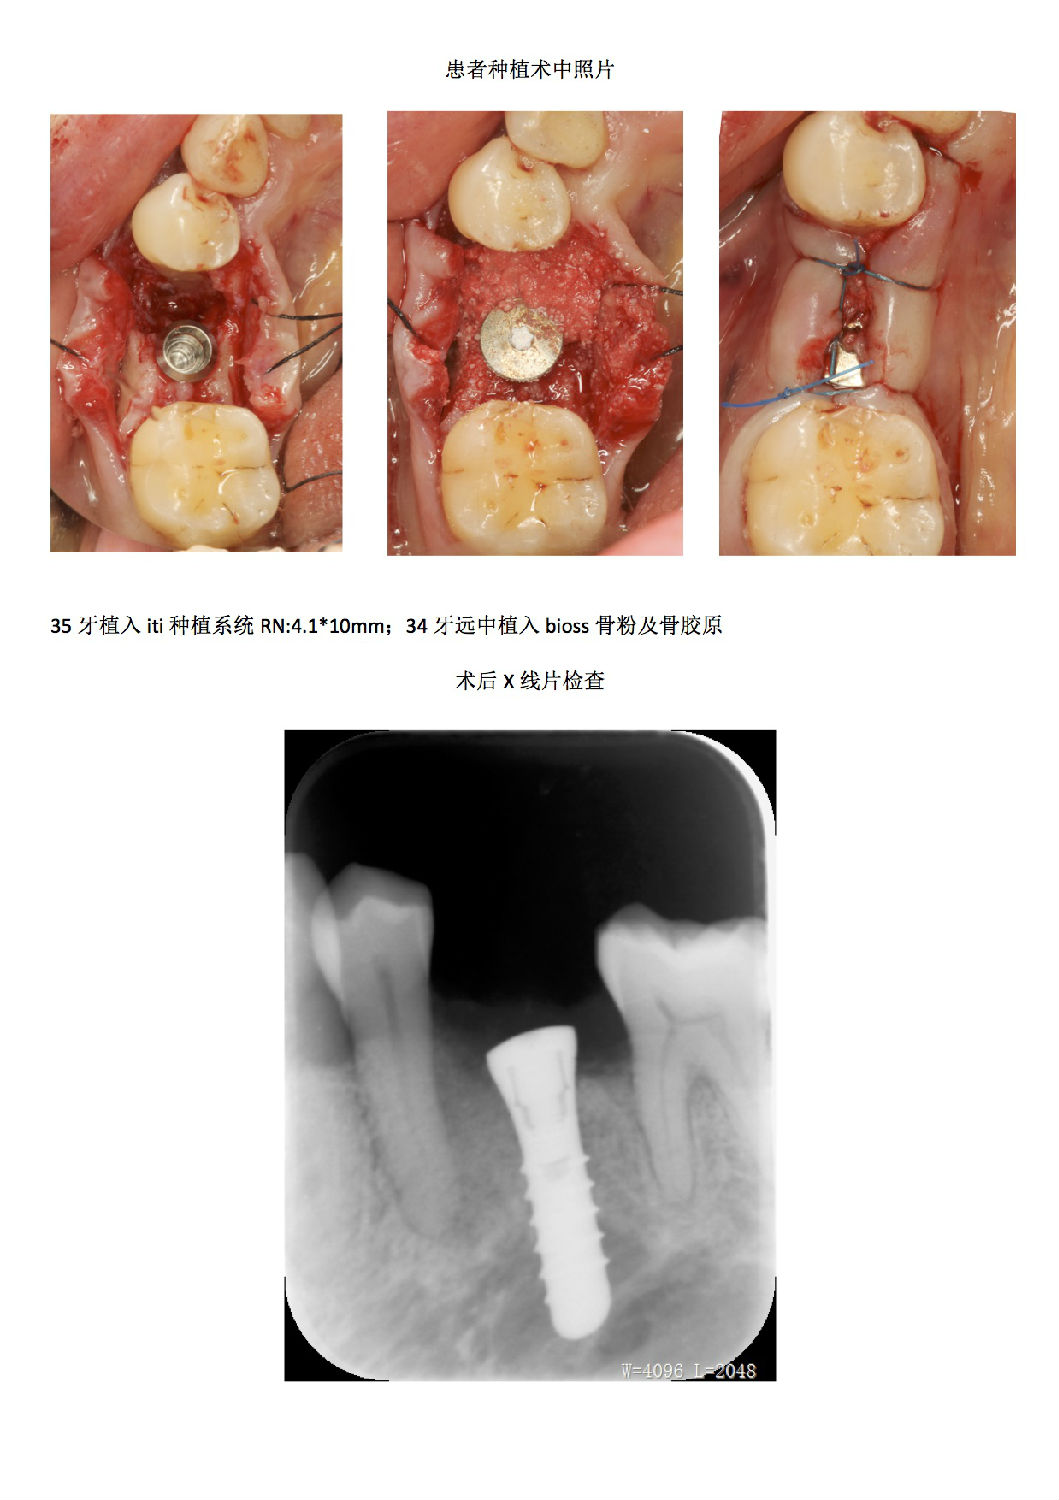

牙周病患者種植治療+鄰牙GTR病例匯報